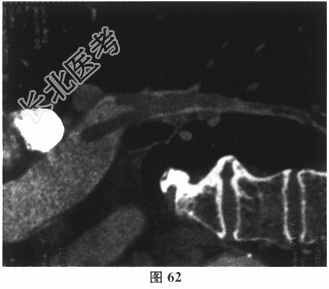

- 多项选择题2.[提示]入院后完善相关检查,心电图: 频发室性期前收缩(图61)。D-二聚体1378μg/L(正常0~500μg/L)。心脏超声示:左房增大, 三尖瓣、肺动脉瓣轻度反流,左室松弛, 功能减退。胸部CT:两肺间质改变, 两侧胸膜增厚。

- 多项选择题3.[提示]入院后持续监测,生命体征平稳, 经对症治疗症状逐渐缓解。进一步检查,下肢深静脉多普勒超声: 右侧腘静脉、胫后静脉多发血栓形成。肺动脉CTA(图62~图65)示双肺动脉分支多发栓塞。冠脉CTA示冠脉多处钙化斑块,前降支中段轻度狭窄。BNP36.8pg/ml(正常0~100pg/ml)。TNI<0.05ng/ml(正常0~0.4ng/ml)。动脉血气分析: 氧分压63mmHg,二氧化碳分压28.7mmHg。